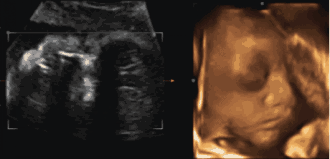

為了提前探尋這一“真相”

我們可以通過一個(gè)特別的儀式

在影像中讓寶寶與爸爸媽媽提前相遇

感受寶寶與父母奇妙的連接

這一切,只需要選擇四維彩超就可以啦

1、四維彩超最佳時(shí)間是孕24—26周。